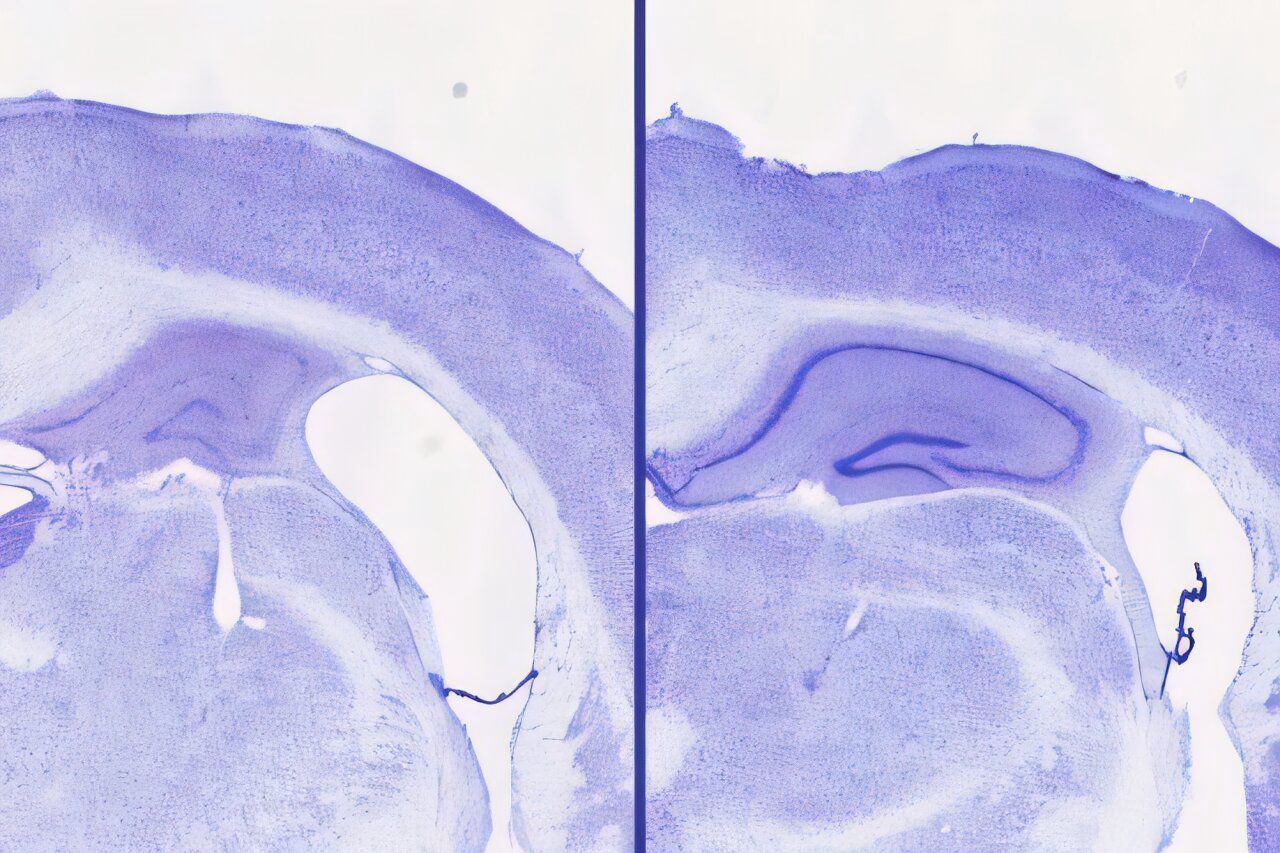

The study demonstrated that mice treated with lemborexant exhibited a 30–40% larger hippocampal volume—a brain region critical for memory—compared to untreated mice. This suggests that the drug not only enhances sleep but also offers neuroprotective benefits by reducing tau accumulation. Interestingly, these effects were observed only in male mice, prompting further investigation into sex-specific responses.